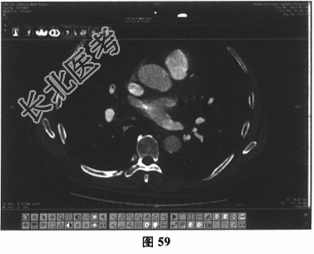

- 多项选择题5.[提示]患者肺动脉CTA(图57~图60):右肺中动脉及右下肺动脉低密度充盈缺损。下肢静脉多普勒超声未见异常。综合上述检查结果, 明确诊断为

A、肺栓塞